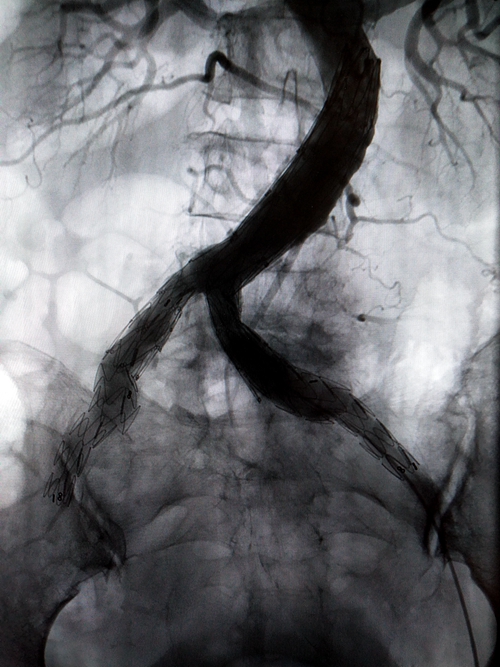

手术过程中

手术在介入手术室进行,由胡康新教授指导,汤金城医生主刀,在DSA引导下,局麻切开右侧股动脉,在超硬导丝引导下置入一体式腹主动脉覆膜支架于腹主动脉末端及双侧髂总动脉内,并在腹主动脉一体式支架远端左右各植入一个覆膜支架,覆盖髂内动脉瘤开口,支架植入后再造影,髂内动脉瘤腔内只少量显影,随着时间的推移双侧髂内动脉瘤开口最终会完全覆盖。手术采取局部麻醉,全程患者并未有痛苦感。经过两个小时的手术,介入医生成功拆除了这两颗“定时炸弹”。

支架植入后造影